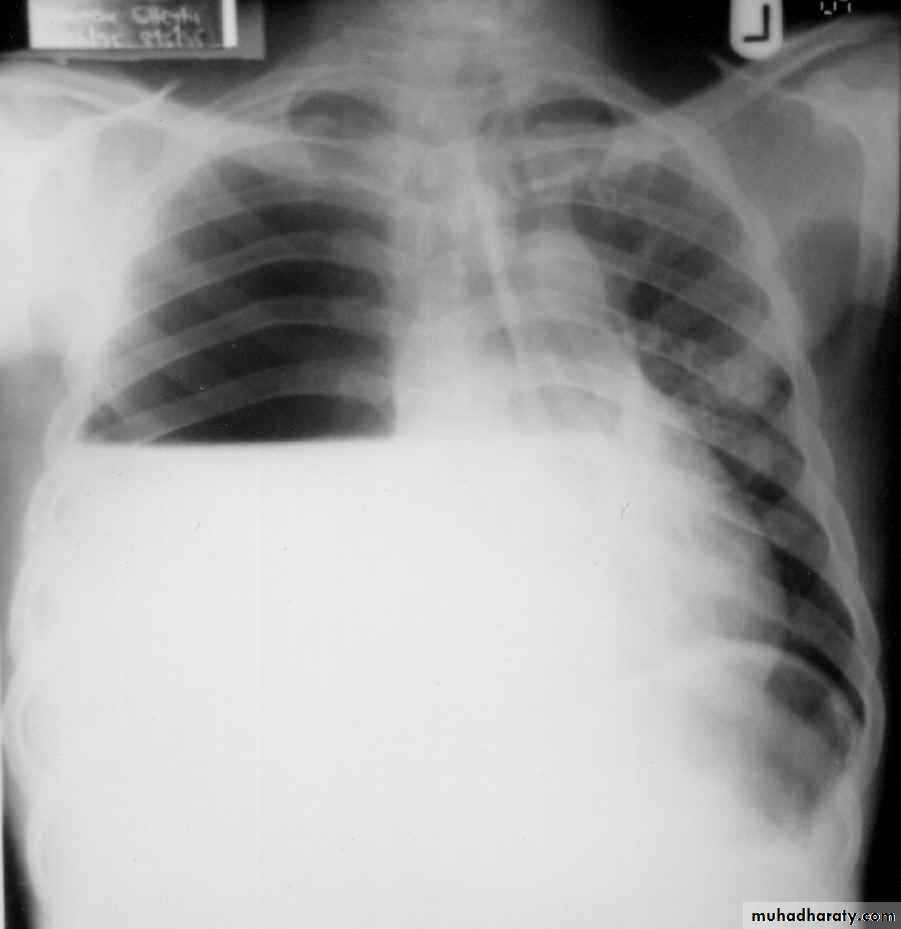

Chest x ray erect position, P-A view: blunting of the costophrenic angle on the right side, occurs once 200 ml of pleural fluid has accumulated.

A homogenous opacification is noted in the right lower zone with the opacity seen to track along the lateral chest wall. The right costophrenic angle is obliterated with a meniscus noted. Findings of a right sided pleural effusion.